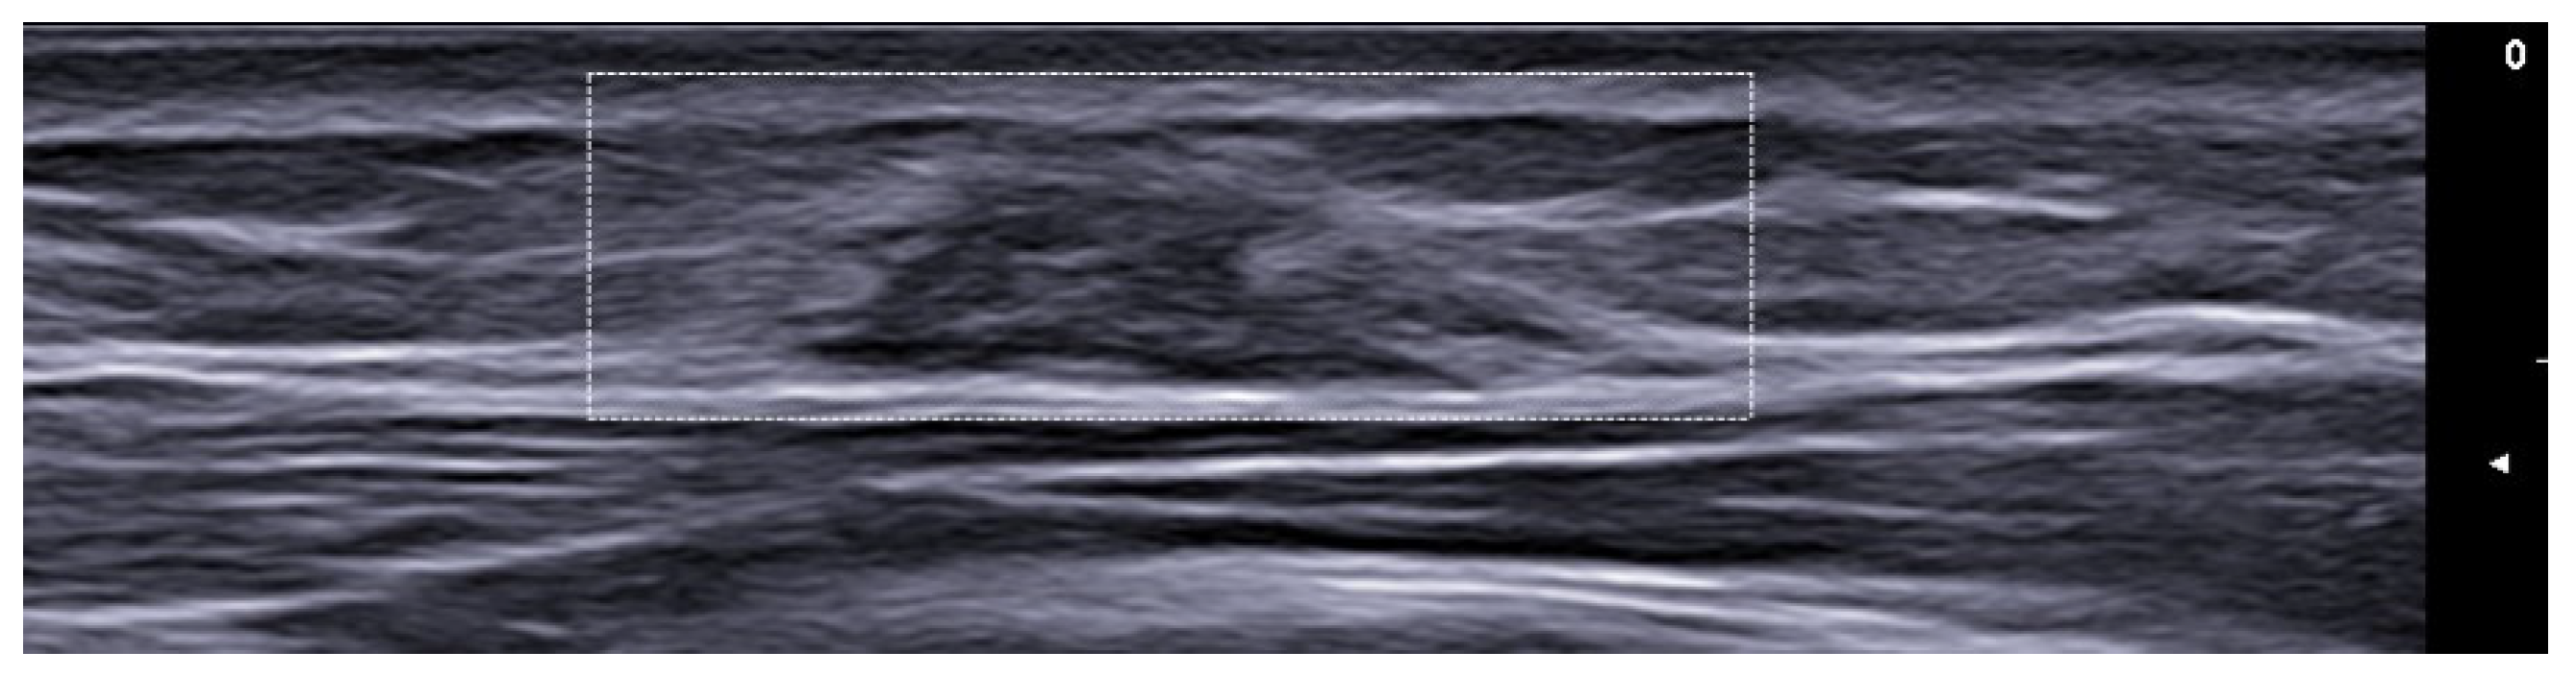

7. External-Agent-Associated Disorders

8. Neoplastic Diseases